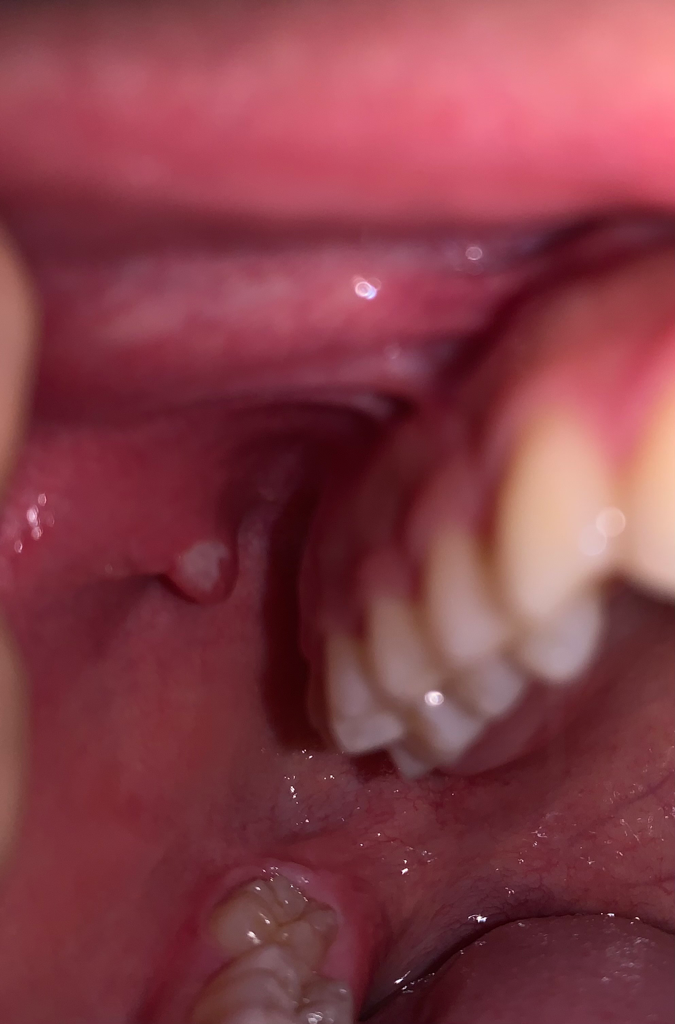

사진의 소견을 통해서 보았을 때에는 구내염 소견 외에는 딱히 구강암을 강력하게 의심할만한 소견이 있어 보이지 않습니다. 그렇지만 우려스럽다면 이비인후과에서 보다 더 정확한 검진 및 감별 진단을 받아보시길 권고드립니다.